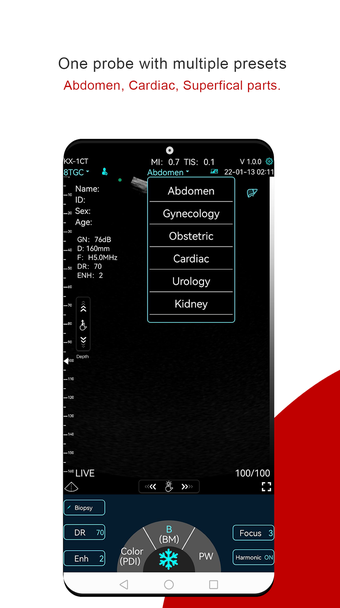

Мой USG — это первое соединение между зондом и интеллектуальному терминальному устройству необходимо ввести пароль Wi-Fi.